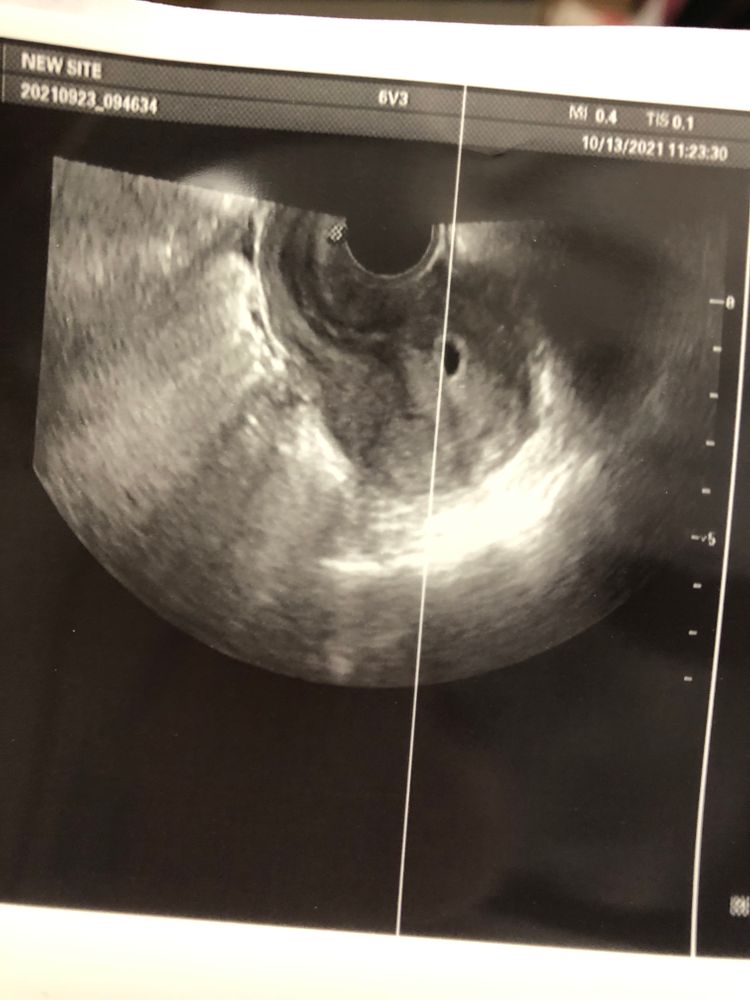

Первое узи

Ну вот. Сделала сегодня узи. По месячным срок 7 недель. А тут 3.1. Еле нашли, потому что матка в загибе. Узистка сказала, что либо у меня поздняя овуляция, ввиду того, что у меня цикл ненормированный(всегда по разному)

либо не развивающаяся.

сказали сдать хгч. Поспешно побежала сдала. Жду результатов, а пока переживаю, лишь бы всё было хорошо 😔